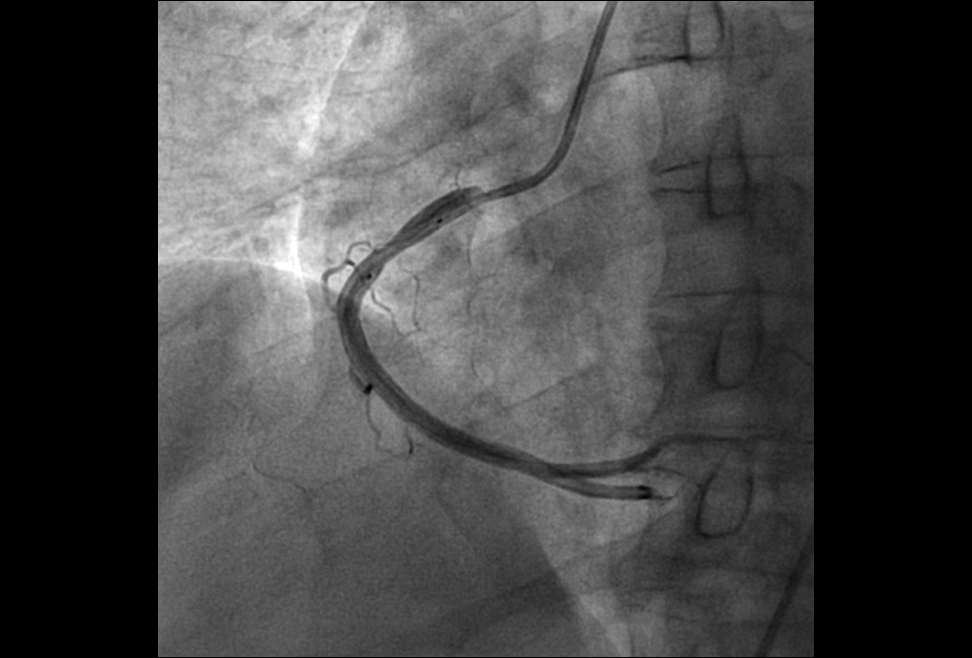

1.心血管介入手术治疗:可以完成冠状动脉造影术,PTCA支架术,二尖瓣球囊扩张术,射频消融术,起搏器植入术,先天性心脏病介入治疗,冠状动脉腔内溶栓术等微创介入手术。

病患的右冠狭窄 通过DSA支架植入 有冠状动脉恢复正常供血,病人病情缓解